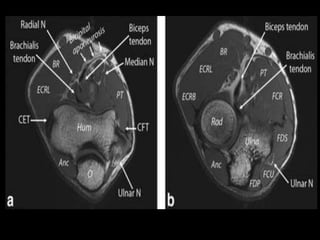

Elbow Joint.

Indication.

-Pain.

-Swelling.

-Stiffness.

-Deformity.

-Instability.

-Paraesthesias.